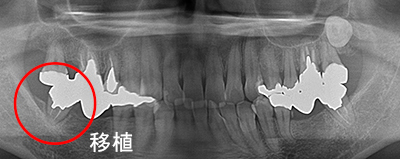

抜歯した親知らずを移植(3)

Before

After

左上の歯が折れています。折れた歯を抜き、親知らずの歯を移植しました。